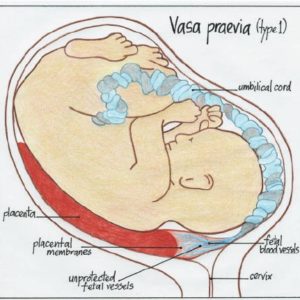

Vasa previa is a whole different kettle of fish. Many people get vasa previa and placenta previa confused, as they sound very similar. Vasa previa is a very rare condition where the blood vessels from baby’s cord lie across or close to the cervical os. Though both conditions are dangerous, vasa previa is arguably more-so (at least for baby) because if these vessels burst then baby can bleed out and die within a matter of minutes. Whereas in placenta previa, there’s usually a bit more time to act before baby is in danger, as it’s the mother’s blood and not the baby’s (baby has less than 300ml when they’re born, so a lot less than an adult!). Velamentous cord insertion refers to the way the cord inserts into the placenta, and often (but not always) this condition goes hand in hand with vasa previa, because the condition makes it more likely the vessels will be close to the cervix. Instead of the cord inserting in the middle of the placenta, the cord runs flat along the uterus and inserts at the edge of the placenta. The vessels are more vulnerable than usual, as at the point of insertion they aren’t tightly bound in a cord.

The vessels can move away from the cervix with growth of the uterus, but it’s a lot less likely. And, like with placenta previa, you can’t have a natural birth with vasa previa. If allowed to have a natural birth, most babies will die when the blood vessels rupture from the pressure of labor. The lucky babies who survive often need blood transfusions and resuscitative measures. So, instead they usually do a caesarean section at 34-36 weeks’ gestation which, thankfully, increases survival rates to 97%.